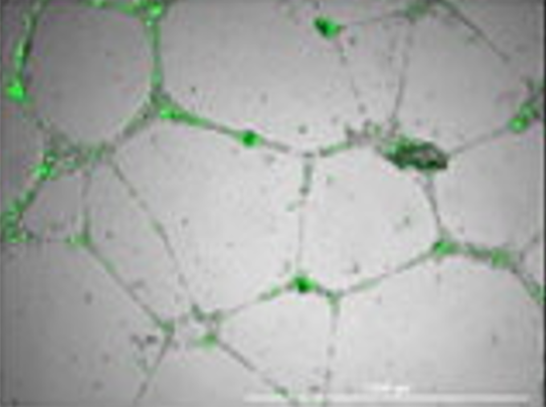

Neuromics Models include Human Blood-Brain Barrier (BBB) and Human Umbilical Vein Endothelial Cells. The models are used to study the penetration rates of pathogens, compounds, proteins, and molecules through the microvascular endothelial cells barrier.

Please note: markers for endothelial change after penetration.